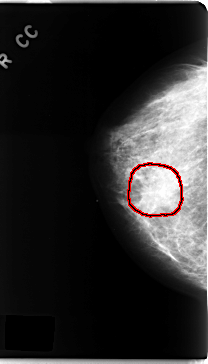

C_0162_1.RIGHT_CC

RIGHT_CC LINES 4720 PIXELS_PER_LINE 2696 BITS_PER_PIXEL 12 RESOLUTION 50 OVERLAY

FILE: C_0162_1.RIGHT_CC.OVERLAY

TOTAL_ABNORMALITIES 1

ABNORMALITY 1

LESION_TYPE CALCIFICATION TYPE FINE_LINEAR_BRANCHING DISTRIBUTION CLUSTERED

LESION_TYPE MASS SHAPE IRREGULAR MARGINS ILL_DEFINED

ASSESSMENT 5

SUBTLETY 4

PATHOLOGY MALIGNANT

TOTAL_OUTLINES 1

BOUNDARY